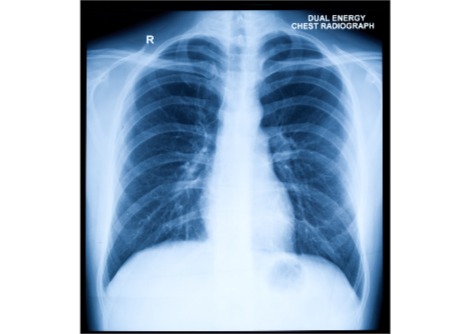

يُعرف مرض الحصبة بطفحه الأحمر المتبقع الذي يبدأ عادةً على الوجه، ويمكن أن يؤدي إلى ارتفاع في درجة الحرارة، والتهاب رئوي، والتهاب في الأذن، وتورم في الدماغ. الفيروس المسبب للحصبة شديد العدوى. ينتشر الفيروس المنتقل عبر الهواء عند ملامسة شخص مريض أو ملامسة أسطح ملوثة بالفيروس. يمكن أن يبقى الفيروس عالقًا في الهواء لساعات حتى بعد مغادرة الشخص المصاب للغرفة. بعد التعرض، يُصاب به ما يصل إلى 90% من الأشخاص الذين لا يمتلكون مناعة ضد الحصبة.